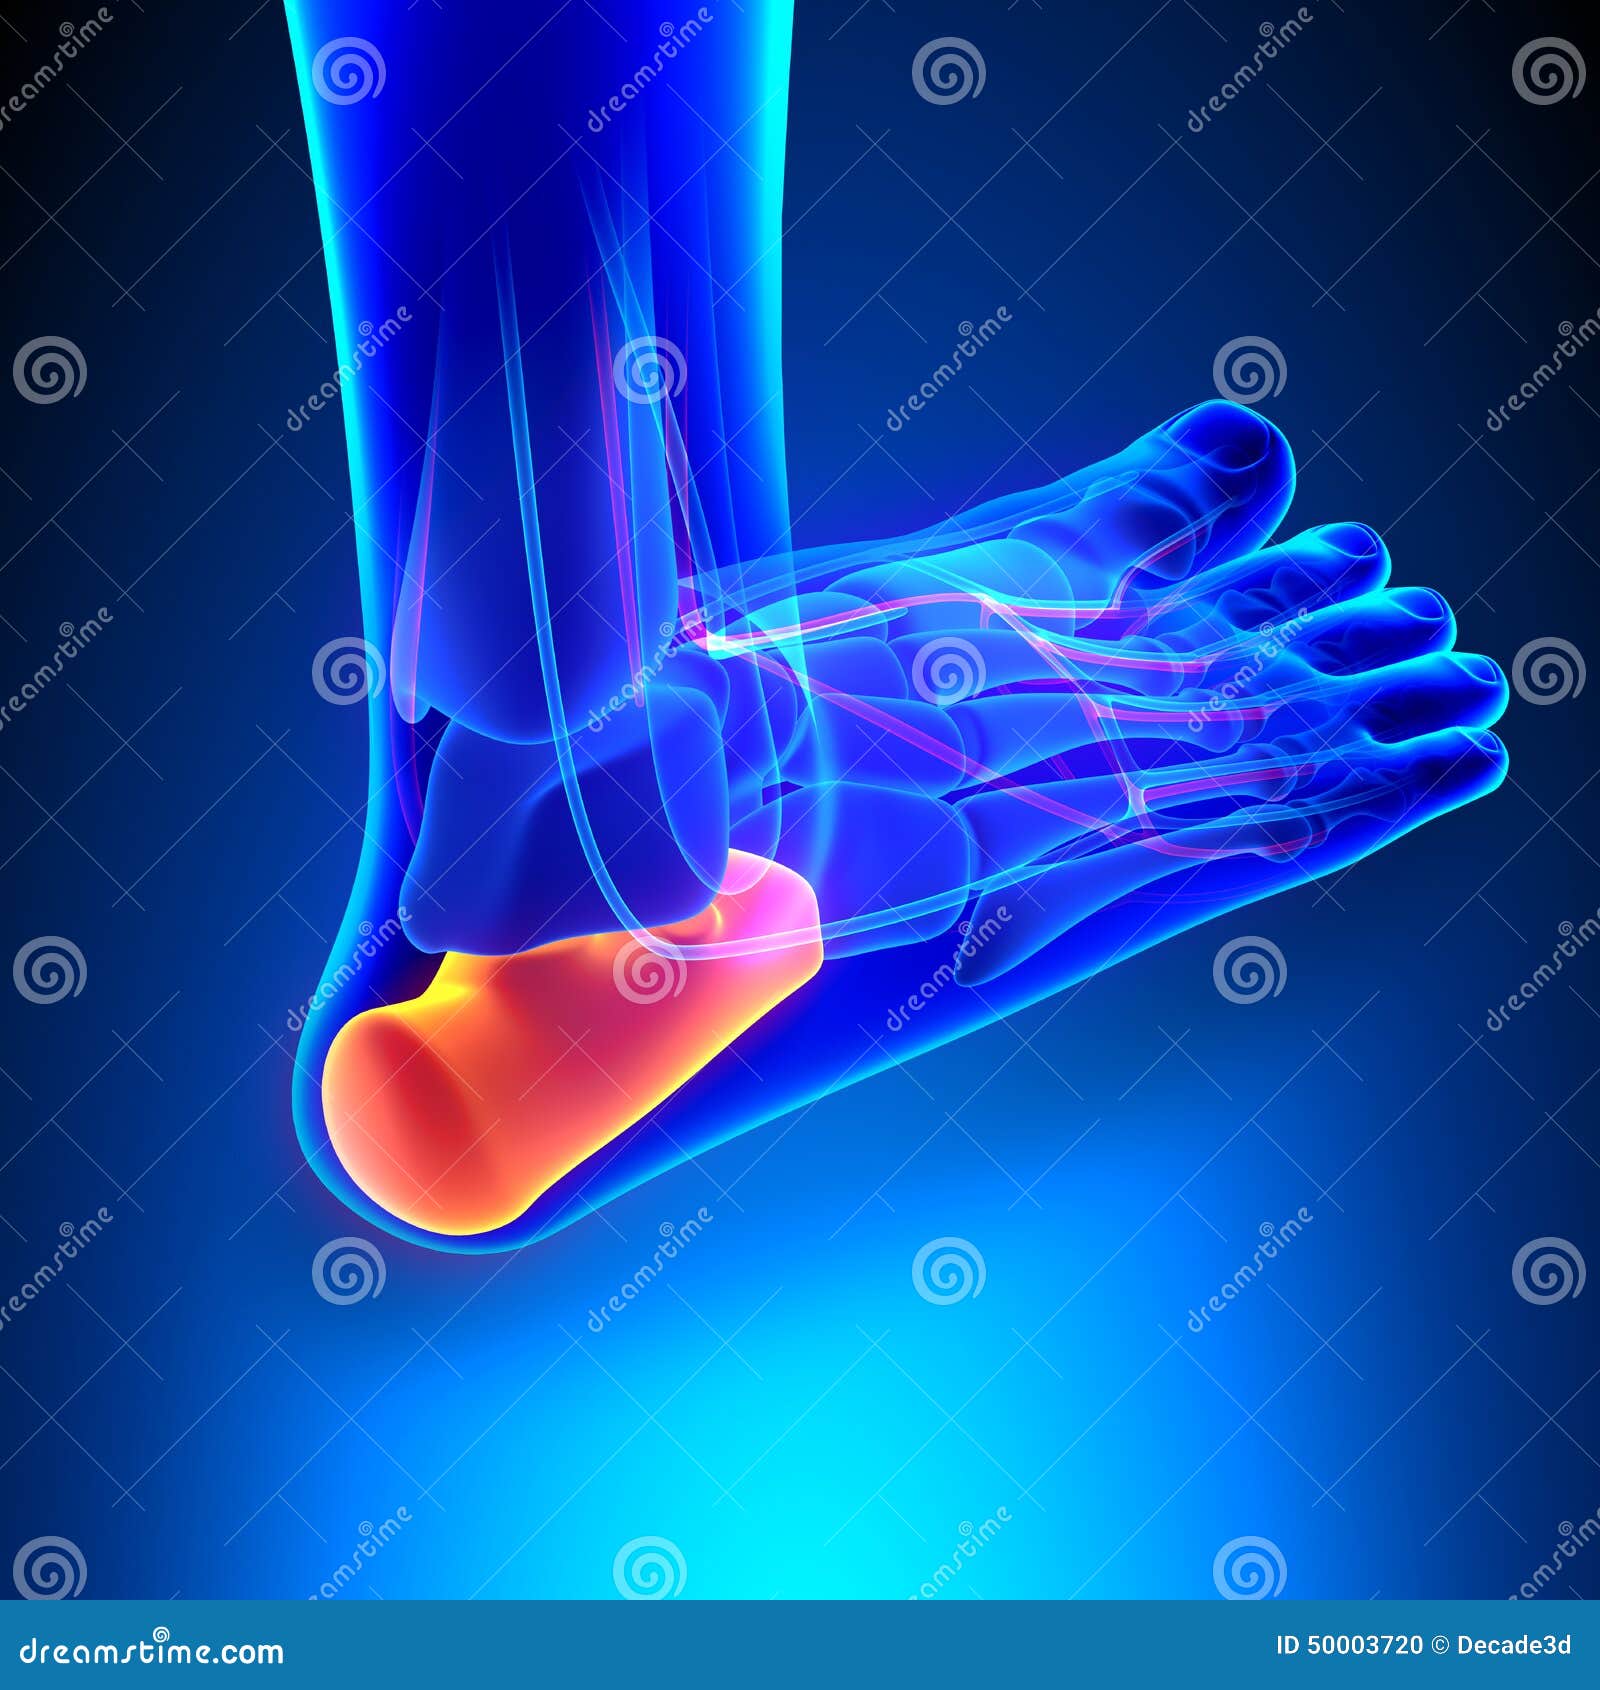

Pain On The Calcaneus Bone . If the pain persists longer than three weeks, it is best to seek professional advice. You might experience pain, soreness or tenderness anywhere in your heel,. Though most heel pain results from inflammation of tissues surrounding the calcaneus (e.g., tendons, bursae, and fasciae), injuries causing calcaneal fracture can occur. It is one of the tarsals, the bones that make up part of the foot and ankle. The calcaneus is the bone that forms the heel of the foot. This type of pain is a common complaint for people of all ages and activity. Heel pain is a very common foot and ankle problem. Learn about side heel pain causes, symptoms, and treatment options. Heel pain causes a throbbing, aching, burning, or stabbing sensation in the back or bottom of the foot. Discover how stress fractures, arthritis, tendon inflammation,. The calcaneus is the largest bone of the foot and provides the foundation for all of the other tarsals

Though most heel pain results from inflammation of tissues surrounding the calcaneus (e.g., tendons, bursae, and fasciae), injuries causing calcaneal fracture can occur. Heel pain causes a throbbing, aching, burning, or stabbing sensation in the back or bottom of the foot. Heel pain is a very common foot and ankle problem. This type of pain is a common complaint for people of all ages and activity. It is one of the tarsals, the bones that make up part of the foot and ankle. The calcaneus is the bone that forms the heel of the foot. Learn about side heel pain causes, symptoms, and treatment options. You might experience pain, soreness or tenderness anywhere in your heel,. Discover how stress fractures, arthritis, tendon inflammation,. If the pain persists longer than three weeks, it is best to seek professional advice.

Pain On The Calcaneus Bone Learn about side heel pain causes, symptoms, and treatment options. It is one of the tarsals, the bones that make up part of the foot and ankle. Discover how stress fractures, arthritis, tendon inflammation,. Heel pain causes a throbbing, aching, burning, or stabbing sensation in the back or bottom of the foot. The calcaneus is the bone that forms the heel of the foot. You might experience pain, soreness or tenderness anywhere in your heel,. This type of pain is a common complaint for people of all ages and activity. Learn about side heel pain causes, symptoms, and treatment options. Heel pain is a very common foot and ankle problem. Though most heel pain results from inflammation of tissues surrounding the calcaneus (e.g., tendons, bursae, and fasciae), injuries causing calcaneal fracture can occur. The calcaneus is the largest bone of the foot and provides the foundation for all of the other tarsals If the pain persists longer than three weeks, it is best to seek professional advice.